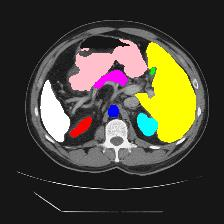

Medical image segmentation is one of the most fundamental tasks concerning medical information analysis. Various solutions have been proposed so far, including many deep learning-based techniques, such as U-Net, FC-DenseNet, etc. However, high-precision medical image segmentation remains a highly challenging task due to the existence of inherent magnification and distortion in medical images as well as the presence of lesions with similar density to normal tissues. In this paper, we propose TFCNs (Transformers for Fully Convolutional denseNets) to tackle the problem by introducing ResLinear-Transformer (RL-Transformer) and Convolutional Linear Attention Block (CLAB) to FC-DenseNet. TFCNs is not only able to utilize more latent information from the CT images for feature extraction, but also can capture and disseminate semantic features and filter non-semantic features more effectively through the CLAB module. Our experimental results show that TFCNs can achieve state-of-the-art performance with dice scores of 83.72\% on the Synapse dataset. In addition, we evaluate the robustness of TFCNs for lesion area effects on the COVID-19 public datasets. The Python code will be made publicly available on https://github.com/HUANGLIZI/TFCNs.

翻译:医学图像分解是医学信息分析的最根本任务之一,到目前为止已经提出了各种解决办法,包括许多深层次的学习技术,如U-Net、FC-DenseNet等。 然而,高精度医学图像分解由于医疗图像中存在固有的放大和扭曲,以及存在与正常组织密度相似的损伤,因此仍是一项极具挑战性的任务。在本文件中,我们建议TFCN(全面革命稠密网络的传输者)通过向FC-DenseNet引进ResLear-Transerferent(R-Transerfor)和Culvacial线性关注区(CLAB)来解决这一问题。TFCN不仅能够利用CT图像中更多的潜在信息来提取特征,而且还能够通过CLAB模块更有效地捕捉和传播语性特征和过滤非神经性特征。我们的实验结果表明,TFCN可以在Syapseion/SymblyDDS上以83CN-72 ⁇ 的分数实现状态。此外,我们在Synapse-DRIS数据设置上,我们还将评估CUTFTFI/LIS的可靠度。